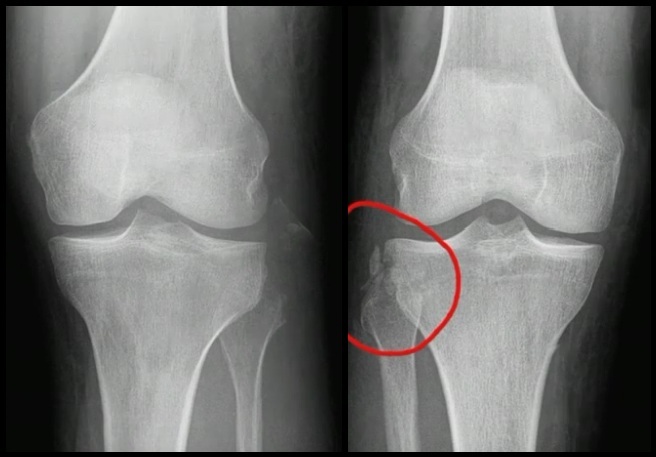

• Sinal do Arqueado: Avulsão da cabeça da fíbula pelo CPL

• Fratura de Segond: Avulsão anterolateral do plato tibial pela cápsula e parte da inserção da banda ileotibial.

Segond → Alta associação com lesão do LCA